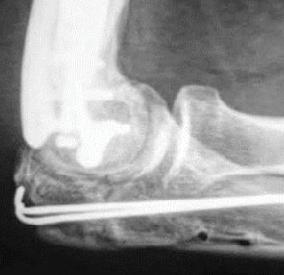

Figura 1 – Măsurători radiologice post-operator, din față și din profil, la un pacient pediatric operat cu procedura Grice

Figura 2 – Măsurători radiologice post-operator, din față și din profil, la un pacient pediatric operat cu procedura Artroerezis

Am analizat retrospectiv pacienții operați în cadrul clinicii noastre pentru picior plat simptomatic între anii 01.01.2013 –01.05.2024 (11 ani). În total, au fost incluși peste 150 de pacienți, dintre care 123 au beneficiat de arthroereisis, iar 34 de procedura Grice. Criteriile de includere au presupus: vârsta pediatrică, deformare simptomatică, lipsa răspunsului la tratament conservator. Examinările radiologice au fost realizate cu piciorul în încarcare si au fost măsurate unghiurile Meary, Kite și Pitch-ul calcanean în radiografia de profil, iar pe radiografia de față unghiul Kite si cel de descoperire al astragalului. Evaluarea clinică s-a bazat pe

• În grupul arthroereisis (n≈123), unghiul Meary a scăzut în medie de la 13° la 4° postoperator, iar unghiul pitch calcanean a crescut de la 11° la 18° (p<0,001 pentru ambele). Aproximativ 85% dintre pacienți au raportat dispariția completă a durerii la 6 luni postoperator.

• În grupul Grice (n≈34), unghiul Meary a scăzut de la 15° la 5°, iar pitch-ul a crescut de la 10° la 16° (p<0,01). Corecția s-a menținut stabilă la controalele la 12 luni.

• Comparativ, pacienții cu arthroereisis au reluat mersul fără durere în medie după 3 săptămâni, în timp ce după Grice acest interval a fost de aproximativ 6 săptămâni (p<0,01).

Complicațiile au fost rare: în grupul arthroereisis, ≈4% dintre pacienți au necesitat explantarea implantului din cauza durerii persistente, cu evoluție bună ulterior; în grupul Grice, ≈12% au avut

consolidare întârziată a grefei osoase, rezolvată conservator.